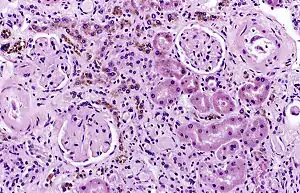

It is only found within cells (as opposed to circulating in blood) and appears to be a complex of ferritin, denatured ferritin and other material.[4][5] The iron within deposits of hemosiderin is very poorly available to supply iron when needed. Hemosiderin can be identified histologically with Perls' Prussian blue stain; iron in hemosiderin turns blue to black when exposed to potassium ferrocyanide.[6] In normal animals, hemosiderin deposits are small and commonly inapparent without special stains. Excessive accumulation of hemosiderin is usually detected within cells of the mononuclear phagocyte system (MPS) or occasionally within epithelial cells of the liver and kidney.

Hemosiderin often forms after bleeding (haemorrhage).[7] When blood leaves a ruptured blood vessel, the red blood cell dies, and the hemoglobin of the cell is released into the extracellular space. Phagocytic cells (of the mononuclear phagocyte system) called macrophages engulf (phagocytose) the hemoglobin to degrade it, producing hemosiderin and biliverdin. Excessive systemic accumulations of hemosiderin may occur in macrophages in the liver, lungs, spleen, kidneys, lymph nodes, and bone marrow. These accumulations may be caused by excessive red blood cell destruction (haemolysis), excessive iron uptake/hyperferraemia, or decreased iron utilization (e.g., anaemia of copper toxicity) uptake hypoferraemia (which often leads to iron deficiency anemia).

Hemosiderin may deposit in diseases associated with iron overload.[8] These diseases are typically diseases in which chronic blood loss requires frequent blood transfusions, such as sickle cell anemia and thalassemia.